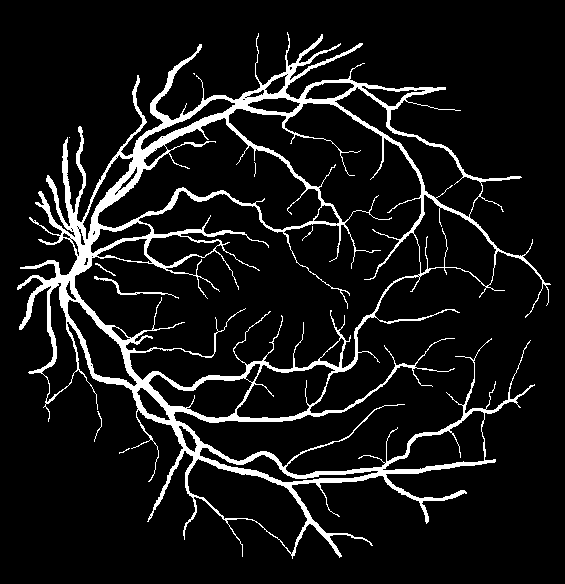

To justify the performance of our model, we compare the 4 metrics with 8 representative previous works from all 3 open-access datasets. The comparison results presented in Table 1 show that our MP-Net model outperforms the state-of-the-art methods regarding accuracy and in all three datasets, which meter the practical prediction quality and the overall prediction quality independent on thresholding specifications. The advancement is greater in the DRIVE dataset. It’s related to the fact that the DRIVE dataset contains more thin vessels, which is the main target of our model. Specificity is also the highest in DRIVE and CHASE_DB1 while sensitivity is highest in STARE. Particularly, our method outperforms ML-UNet [2] and JL-UNet [4] which adopt a different multi-class approach to also especially tackle the thin-vessels challenge. Figure 2 shows an example of our segmentation maps on DRIVE. As can be seen, most thin vessels and boundary areas have been meticulously picked up.